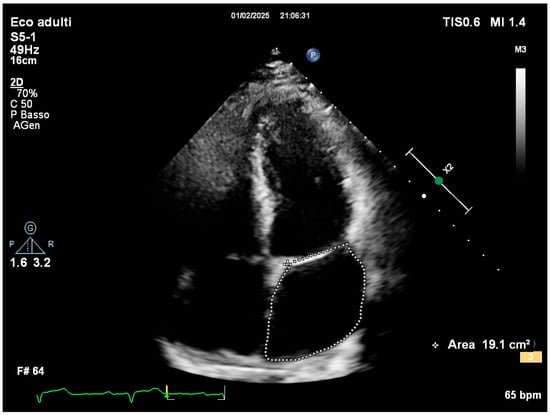

2. Case Presentation